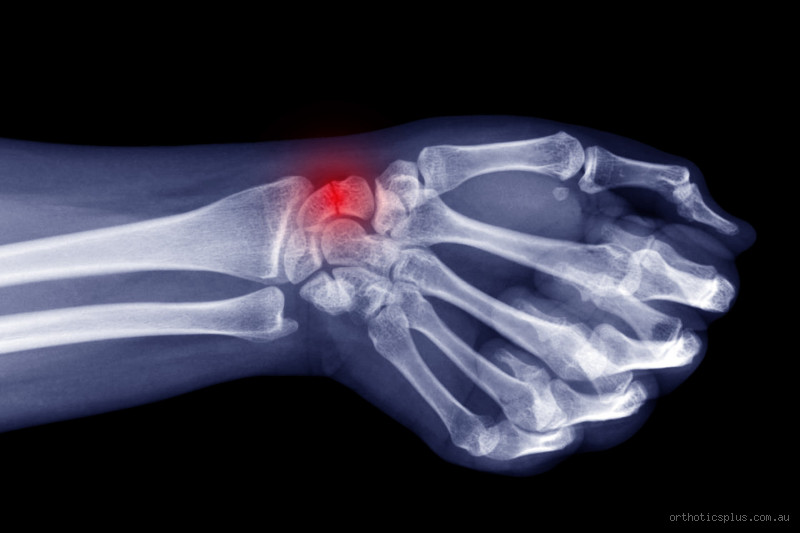

Understanding a Broken Wrist: What Happens to Your Bones?

Okay, so first things first. When you break your wrist, the bones in your forearm (the radius or ulna) can break in different ways. Some fractures are simple, where the bone is cracked but not displaced, while others may involve shattered or displaced bones. In either case, your body begins its natural healing process, but how it heals depends on the severity of the fracture.

Scaphoid fracture: This one involves the small bone on the thumb side of the wrist and is notorious for taking longer to heal.